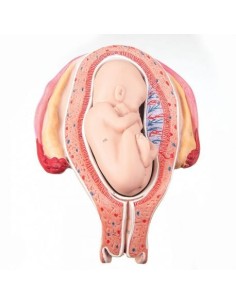

3B Modèle scientifique et anatomique du développement de l'embryon en 12 étapes VG391

3B Modèle anatomique scientifique du bassin gravide, décomposable en 3 parties L20

3B Scientifique, stades de la fertilisation et de la germination, agrandi 2 fois L01